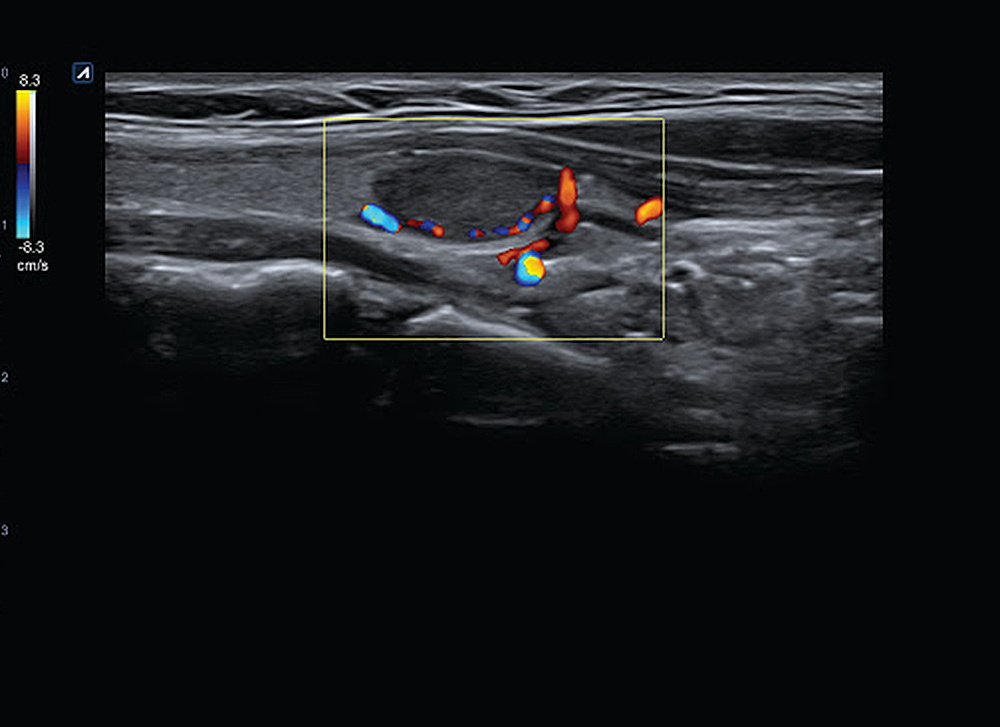

En la cara hay muchos vasos sanguíneos y sin ecografía son imposibles de detectar. Cada vez que se realiza una inyección de relleno sin ecografía, se administra intuyendo la anatomía de cada paciente. Pero hay un gran problema, que todos los seres humanos tenemos variaciones anatómicas . En clínica integral lo primero que hacemos es hacerte una exploración ecográfica del estado de tus tejidos internos (grasa, músculos, vasos sanguíneos,…) para tener el control absoluto de tu anatomía.

Una vez explorado, utilizamos la ecografía para salvar los vasos sanguíneos importantes que nos va marcando la pantalla y vamos dejando el relleno en el plano adecuado donde debe estar.

El ultrasonido puede trazar la ubicación de los vasos sanguíneos más grandes en la cara, por lo que el inyector puede evitar estos vasos durante la inyección de relleno. Esto se conoce como inyección guiada por ultrasonido.